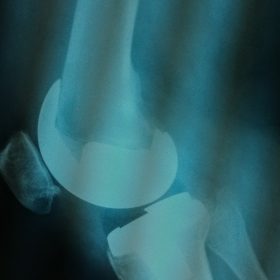

Παρόλα αυτά στην πλειονότητα των περιπτώσεων, με την πάροδο του χρόνου οι παραπάνω τρόποι αντιμετώπισης καθίστανται αναποτελεσματικοί. Η ένταση του πόνου και ο αντίκτυπος στην καθημερινότητα γίνονται αφόρητα.

Σε αυτό το σημείο η Αρθροπλαστική Γονάτου αποτελεί μονόδρομο.